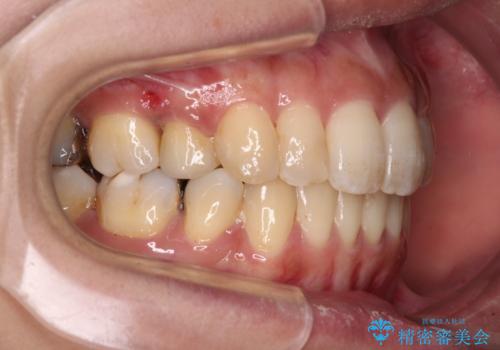

後戻りで突出した前歯をインビザラインで解消

- 抜歯矯正の後戻りで前歯が突出してきていることを気にして来院された患者様です。

口元の突出感を改善するにあたり、抜歯矯正は行うことができないため、奥歯の後方移動とIPR(歯と歯の間を削る)により達成することとしました。

再度後戻りしたときに対応しやすいよう、インビザラインにて矯正治療を行うこととしました。

舌の突出癖がなかなか改善できず、IPRによる前歯の隙間が閉じきらずに、予定よりも長い治療期間となりました。